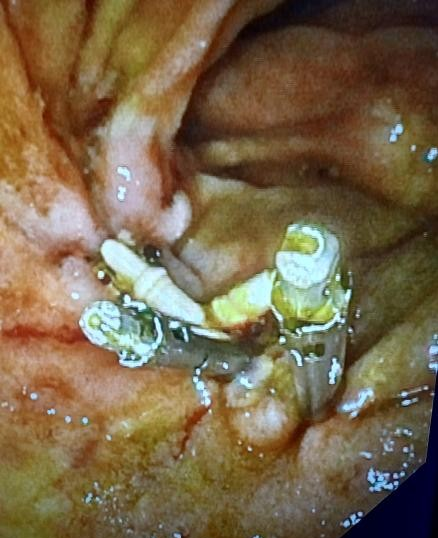

The gastroscope with transparent cap at the end was advanced into the second portion of the descending duodenum. The large adenomatous polyp was seen occupying the majority of the lumen of the duodenum (Figure 2). We then injected epinephrine mixed with lifting agent (Eleview, Cosmo Pharmaceutical, NV), and raised the lesion (Figure 3), and then using 30 mm Captivator snare (BostonScientific) piecemeal resection was done and the entire lesion was successfully excised (Figure 4).  The minimal bleeding during the resection was treated by coagulation grasper (Olympus America) using soft coagulation mode (ERBE USA).  Then we retrieved all these lesions using Roth net.  We retrieved close to 7 cm of this large polyp (Figure 5).  After removing all the polyps the mucosal defect was closed using through the scope suturing device X tack (Boston Scientific).  There was a small margin at the end and it was closed by two Mantis clips(BostonScientific), (Figure 6).  Patient tolerated the procedure well there was no immediate complication. The histopathological examination revealed it was an adenoma with low grade dysplasia and no evidence of malignancy.

Figure 6. Mucosal closure using X tack  and mantis clips